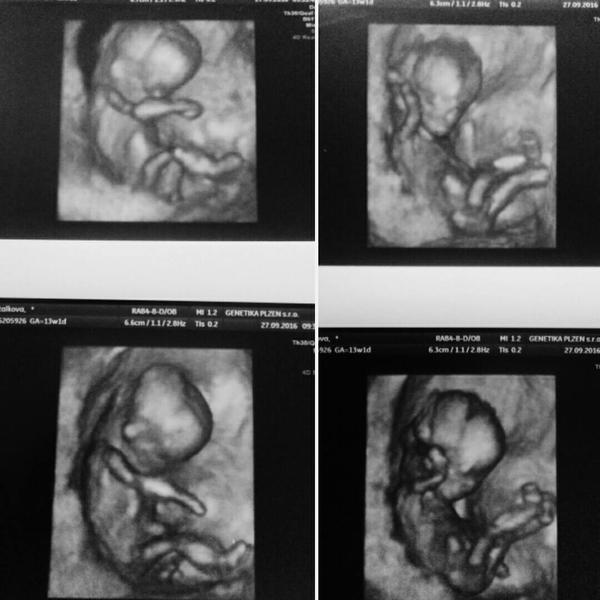

Je to holčička nebo chlapeček? Foto ultrazvuku

@aldri to je tak 13 tt to pozna zkuseny dr.dle hrbolku a ani ten ne nekdy

Podle dr. na screeningu nam bylo jen naznačeno že by to mohl byt chlapec, ale dr byla dost mladá tak se zkusím poptat meho gynekologa zítra na kontrole 🙂 Jinak při prohliženi fotek doma jsem si taky byla jista že to je pindík, ale když ono to prej vypada ve 14t stejně....

@aldri v tomhle týdnu nemají ještě pohlaví vyrysovany, naše holčička tam taky mela "pindika", ale smeroval dolu. U vas směřuje nahoru, priklanim se k chlapeckovi 🙂

@g_m na spodni fotce vlevo jde krasně vidět mezi nožky🙂 chce to jen pořadně koukat🙂

@aldri ja si taky myslim, ze to vypadá na kluka, pohlavni hrbolek směřuje nahoru...ale těžko říct, tak uvidíš 🙂 me to třeba doktor neřekl (jen si tipnul,ze se tam neco mihlo) ani ve 20.týdnu, protože se nam pořád schovává, ale příští tyden ve čtvrtek jdu na 3D, tak snad se mimco umoudri a odhalí, co ma mezi nozkama 😀

@nikyta159 no podle screeningu a uhlu to vypada na chlapečka, tak už koukame spíš po klučičich věcičkach, přece jen pro holčičku to je pak "snažší" : kdyby nahodou:D